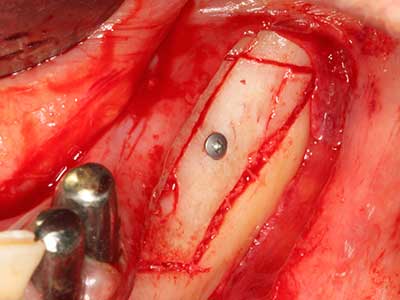

Quando le procedure chirurgiche vengono eseguite sull'osso nelle immediate vicinanze di strutture sensibili, come vasi sanguigni o nervi, gli strumenti rotanti pongono un rischio significativo di lesione iatrogena. I dispositivi piezoelettrici possono essere utili per la preparazione delle coperture ossee e la rimozione del tessuto duro in prossimità dei nervi, in particolare per la loro esposizione dopo una lesione iatrogena, ma anche durante la lateralizzazione dei nervi per le procedure di resezione e ricostruzione o il posizionamento di impianti (figg. 17-20). Il contatto leggero tra puntina piezoelettrica e nervo non causa generalmente danni, ma se si procede senza prestare attenzione con movimenti a sega o raccordi con residui di substrati ossei possono verificarsi danni al nervo temporanei o anche permanenti. Il rischio di danno, tuttavia, è considerato sostanzialmente inferiore al rischio presente utilizzando seghe o frese (Pereira, Gealh et al. 2014).